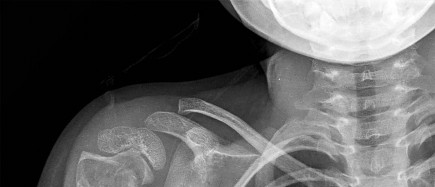

An 19-year-old male presents to the emergency room following an motor vehicle accident as an unrestrained driver. Examination reveals unilateral jugular vein engorgement. Chest and special view

radiographs are seen in Figures A and B respectively. Following CT scan of the chest, the next step in management is